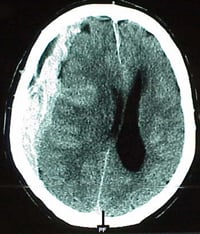

Vid misstanke på att till exempel blödningen ökat intrakraniellt undersöks patienterna med datortomografi.

Datortomografibild på hjärnan.

Datortomografibilden visar en blödning mellan hjärnan och skallbenet.